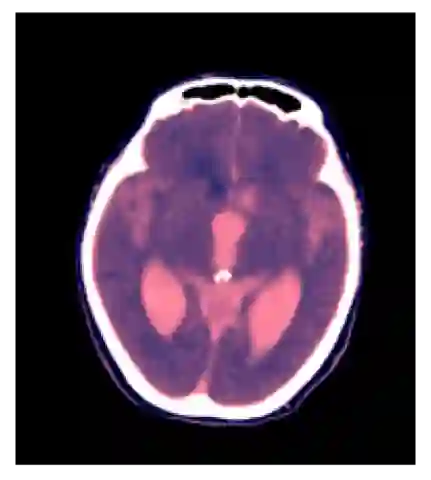

We present an effective method for Intracranial Hemorrhage Detection (IHD) which exceeds the performance of the winner solution in RSNA-IHD competition (2019). Meanwhile, our model only takes quarter parameters and ten percent FLOPs compared to the winner's solution. The IHD task needs to predict the hemorrhage category of each slice for the input brain CT. We review the top-5 solutions for the IHD competition held by the Radiological Society of North America(RSNA) in 2019. Nearly all the top solutions rely on 2D convolutional networks and sequential models (Bidirectional GRU or LSTM) to extract intra-slice and inter-slice features, respectively. All the top solutions enhance the performance by leveraging the model ensemble, and the model number varies from 7 to 31. In the past years, since much progress has been made in the computer vision regime especially Transformer-based models, we introduce the Transformer-based techniques to extract the features in both intra-slice and inter-slice views for IHD tasks. Additionally, a semi-supervised method is embedded into our workflow to further improve the performance. The code is available in the manuscript.